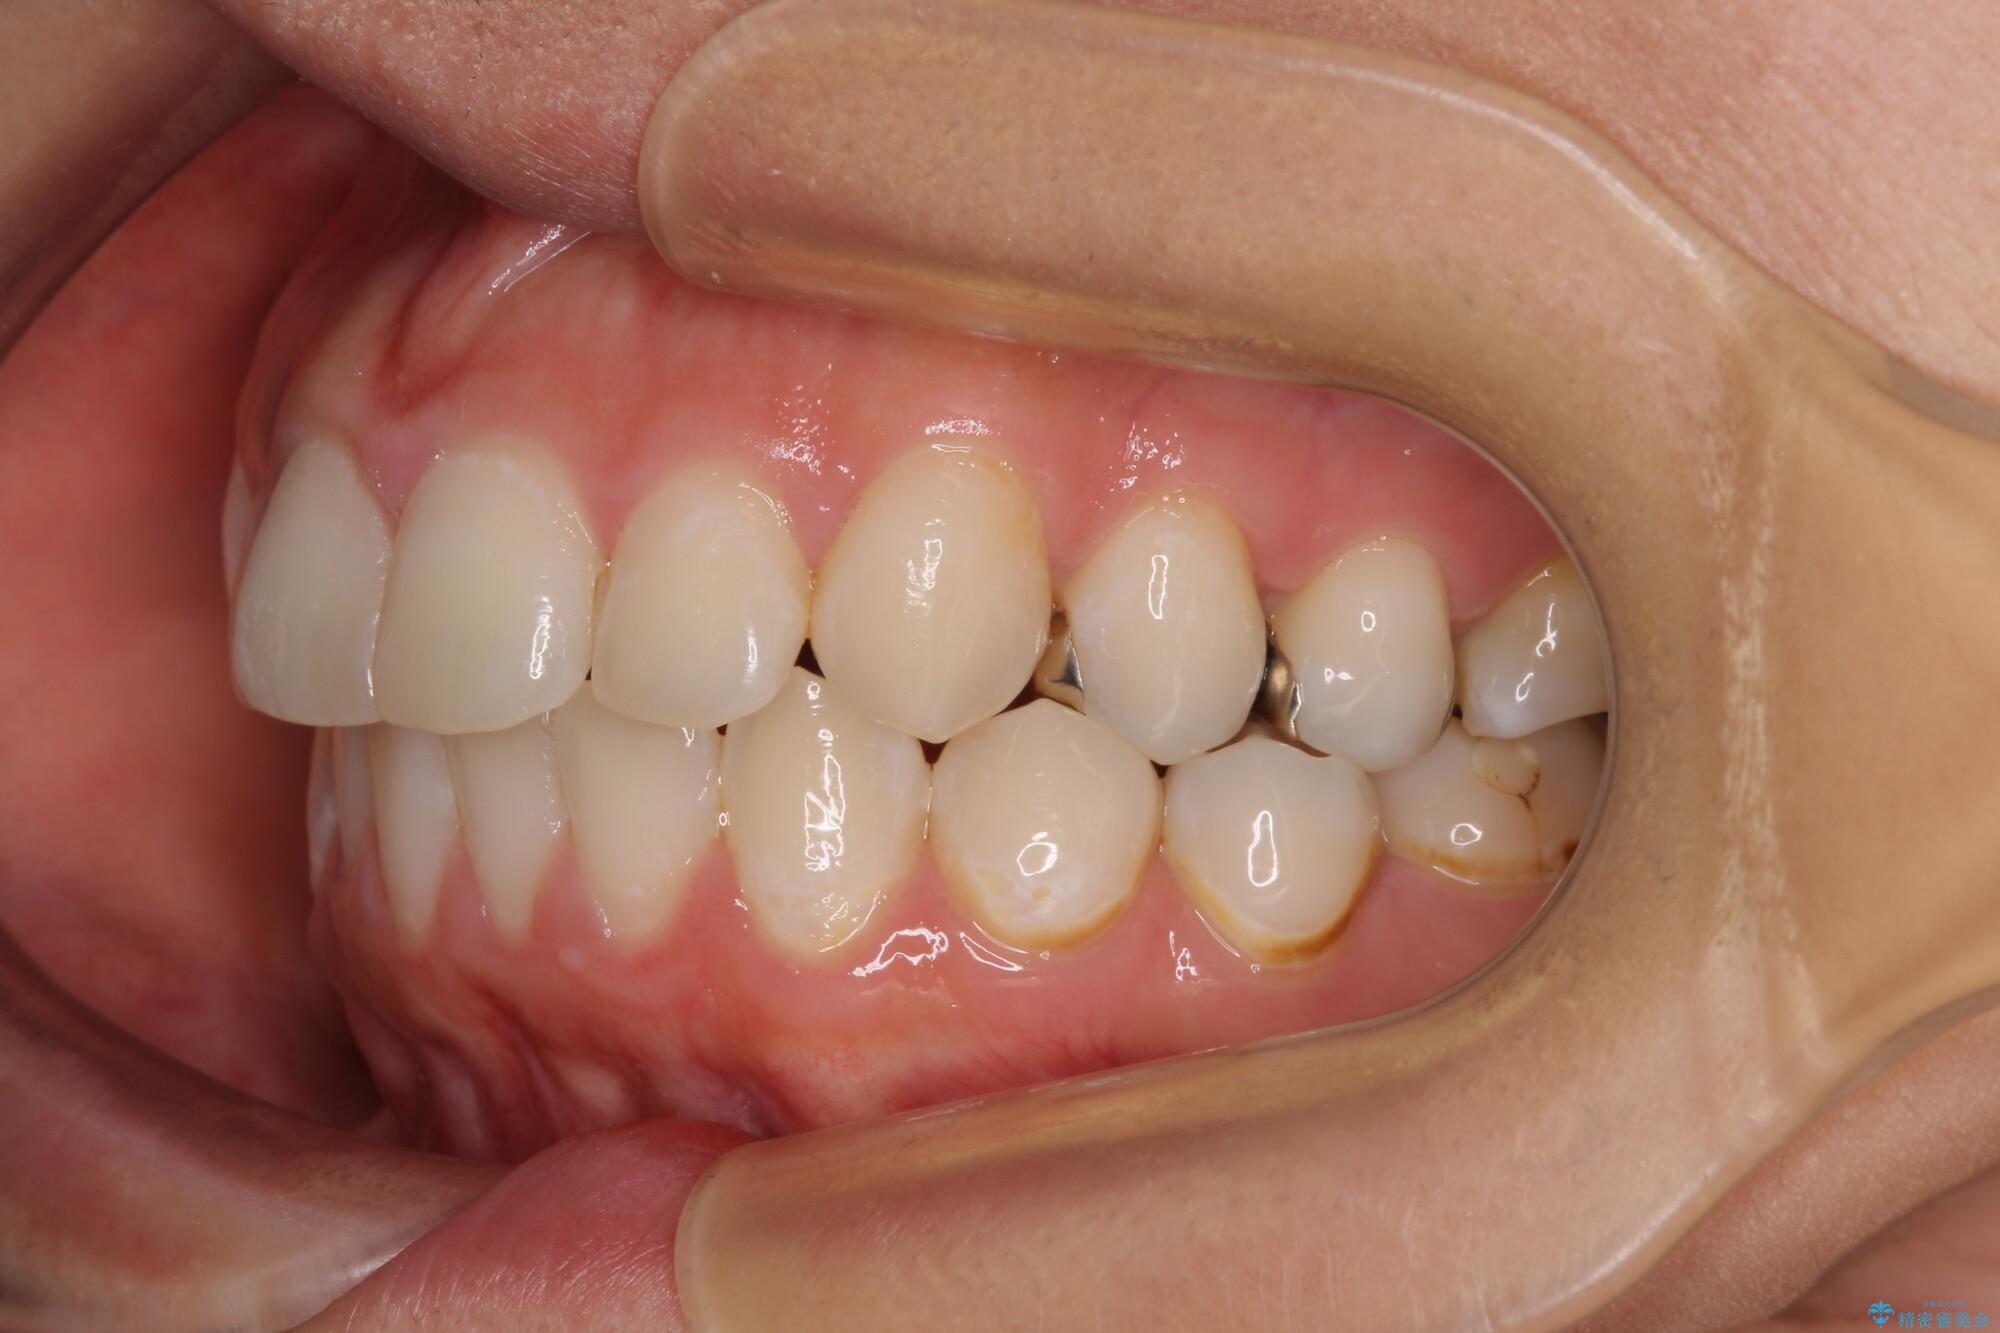

出っ歯と奥歯のむし歯 ワイヤー装置での抜歯矯正とセラミック治療

第二小臼歯抜歯はイレギュラーな治療手段であり、治療期間が延びる傾向にありますが、予定よりも早い2年間で終えることができました。